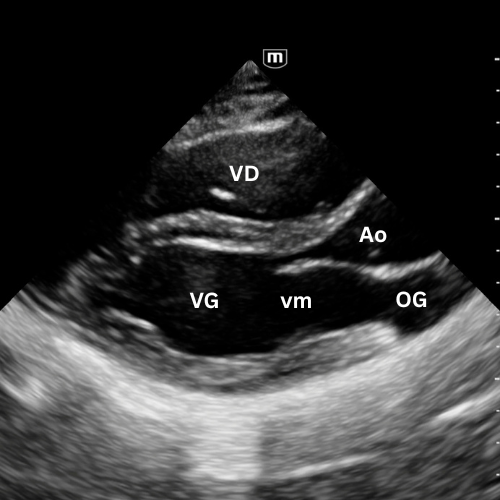

🔹 Vue Parasternale Grand Axe

→ Le cœur se contracte-t-il correctement ?

Sonde au 3ᵉ–4ᵉ espace intercostal gauche, bord sternal, marqueur vers l’épaule droite.

Montre le VG, le VD antérieur, l’oreillette gauche, la valve mitrale, la valve aortique et la racine de l’aorte.

On y évalue :

- la contractilité du VG ;

- la présence d’un épanchement péricardique postérieur ;

- l’aspect de la racine aortique (dilatée, disséquée, hyperéchogène) et la mesure de la chambre de chasse du VG.